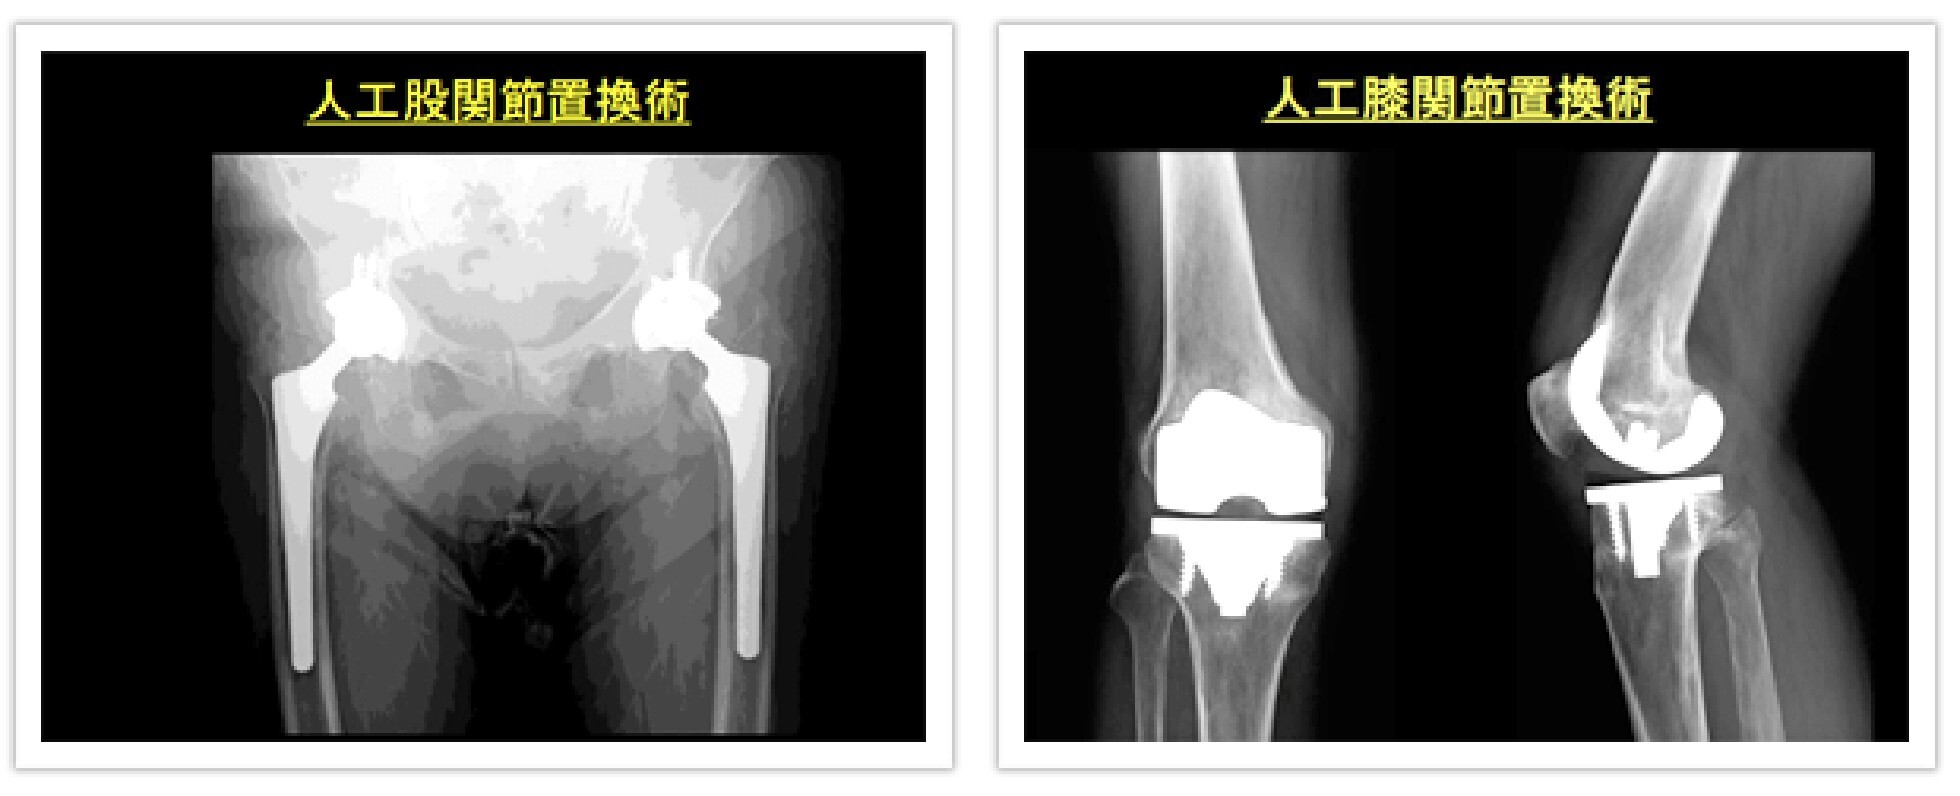

当院では、薬による治療から、リハビリ、手術的治療(関節鏡による滑膜切除、関節温存足趾形成術、腱断裂の手術、膝・股・肩・肘関節などの人工関節置換術)まで症状に応じた治療を行っています。